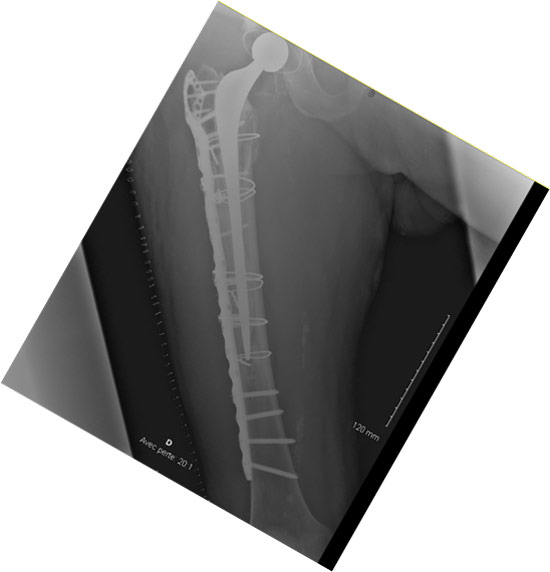

How would you manage this condition?

• ✔️Surgical stem revision and femoral ORIF with a plate

Final strategy decision

• In this case, we decided to perform a unipolar revision and ORIF with a plate (NCB Zimmer) and a cemented revision stem (Exeter Stryker), due to the extension of the fracture beyond the femoral isthmus.

• The patient was asked to avoid weight-bearing for 3 weeks.

• At 6 weeks post-op he was able to walk with one crouch

Postoperative imagery